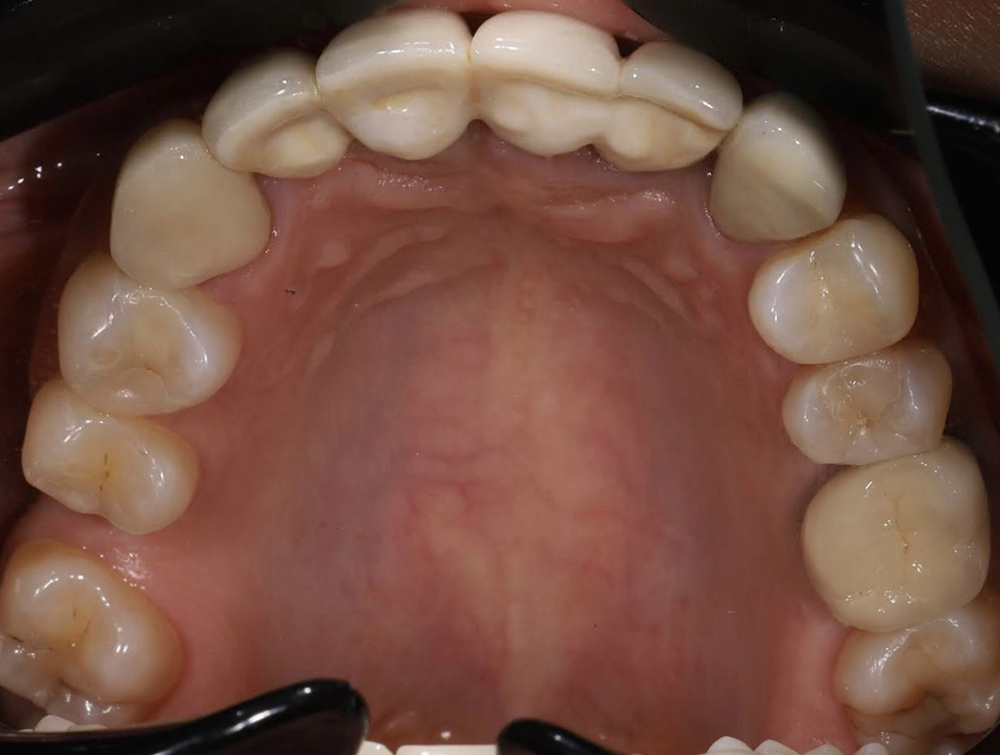

Примеры работ